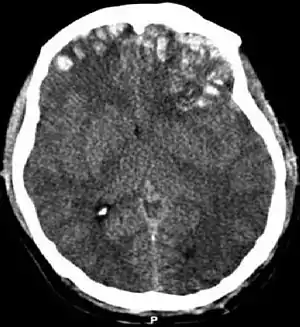

Movement disorders that may develop after TBI include tremor, ataxia (uncoordinated muscle movements), spasticity (muscle contractions are overactive), myoclonus (shock-like contractions of muscles), and loss of movement range and control (in particular with a loss of movement repertoire).[31][33] The risk of post-traumatic seizures increases with severity of trauma (image at right) and is particularly elevated with certain types of brain trauma such as cerebral contusions or hematomas.[34] People with early seizures, those occurring within a week of injury, have an increased risk of post-traumatic epilepsy (recurrent seizures occurring more than a week after the initial trauma).[35] People may lose or experience altered vision, hearing, or smell.[24]

Diffuse injury manifests with little apparent damage in neuroimaging studies, but lesions can be seen with microscopy techniques post-mortem,[94][95] and in the early 2000s, researchers discovered that diffusion tensor imaging (DTI), a way of processing MRI images that shows white matter tracts, was an effective tool for displaying the extent of diffuse axonal injury.[96][97] Types of injuries considered diffuse include edema (swelling), concussion and diffuse axonal injury, which is widespread damage to axons including white matter tracts and projections to the cortex.[98][99]

Hematomas, also focal lesions, are collections of blood in or around the brain that can result from hemorrhage.[24] Intracerebral hemorrhage, with bleeding in the brain tissue itself, is an intra-axial lesion. Extra-axial lesions include epidural hematoma, subdural hematoma, subarachnoid hemorrhage, and intraventricular hemorrhage.[105] Epidural hematoma involves bleeding into the area between the skull and the dura mater, the outermost of the three membranes surrounding the brain.[24] In subdural hematoma, bleeding occurs between the dura and the arachnoid mater.[32] Subarachnoid hemorrhage involves bleeding into the space between the arachnoid membrane and the pia mater.[32] Intraventricular hemorrhage occurs when there is bleeding in the ventricles.[105]